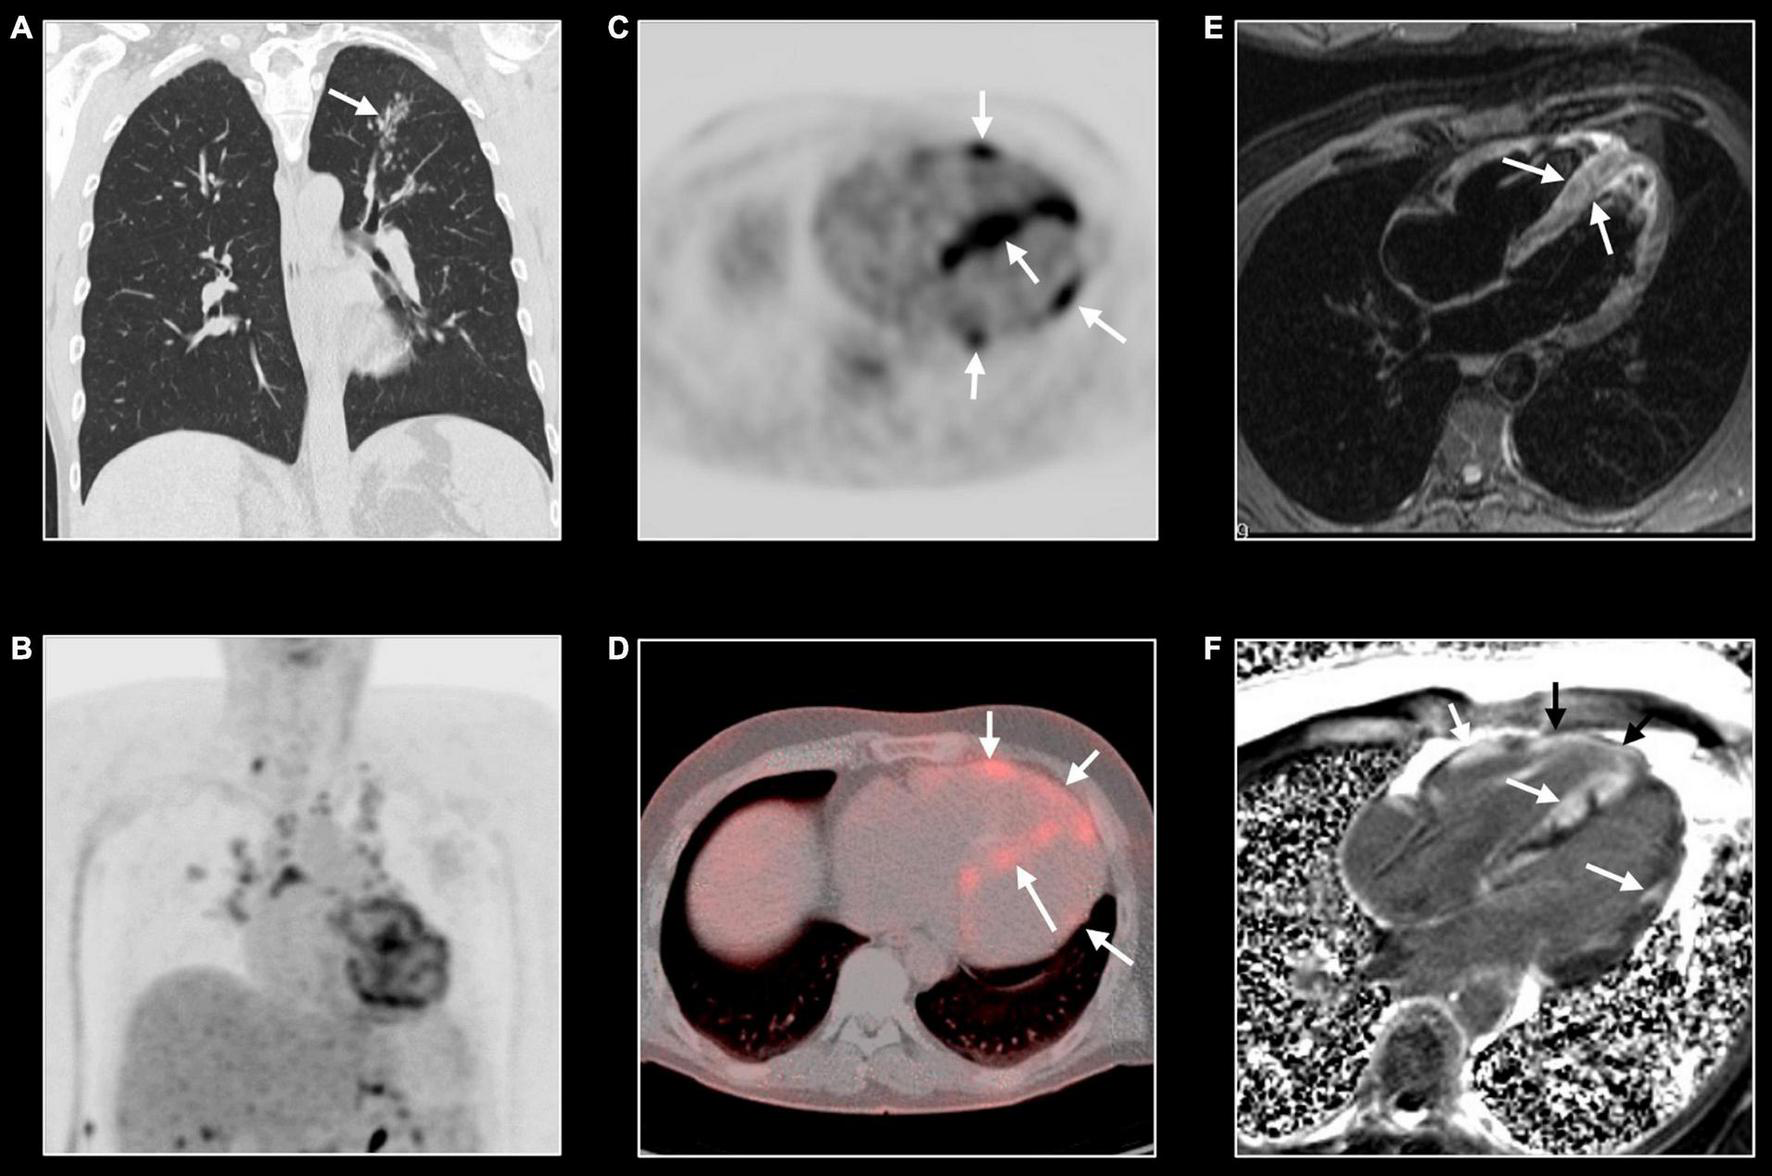

FIGURE 8

Cardiac sarcoidosis. Forty-three-year-old man known with systemic sarcoidosis admitted with recurrent ventricular tachycardia. Chest CT (A) shows enlarged mediastinal lymph nodes and perilymphatic micronodular pattern in left upper lobe (arrow), right middle and lower lobe. Fluoro-deoxy-gluclose (FDG) PET/CT shows multifocal FDG uptake in mediastinal and hilar lymph nodes (B), and strong multifocal uptake in the myocardium of left and right ventricle [arrows, (C,D)]. T2w-imaging shows myocardial edema, most pronounced in the apical half of a thickened ventricular septum [arrows, (E)] while LGE imaging shows multifocal, pronounced myocardial enhancement in left and right ventricle [arrows, (F)]. CMR and PET/CT findings are strongly suggestive of cardiac sarcoidosis with severe biventricular involvement. Cardiac biopsy showed granulomatous myocarditis. Because of the cardiac arrhythmias, the patient received an ICD implantation with several appropriate shocks. Unfortunately, the patient evolved toward biventricular heart failure for which he underwent a heart transplantation. Eight years later, the clinical history is uneventful.